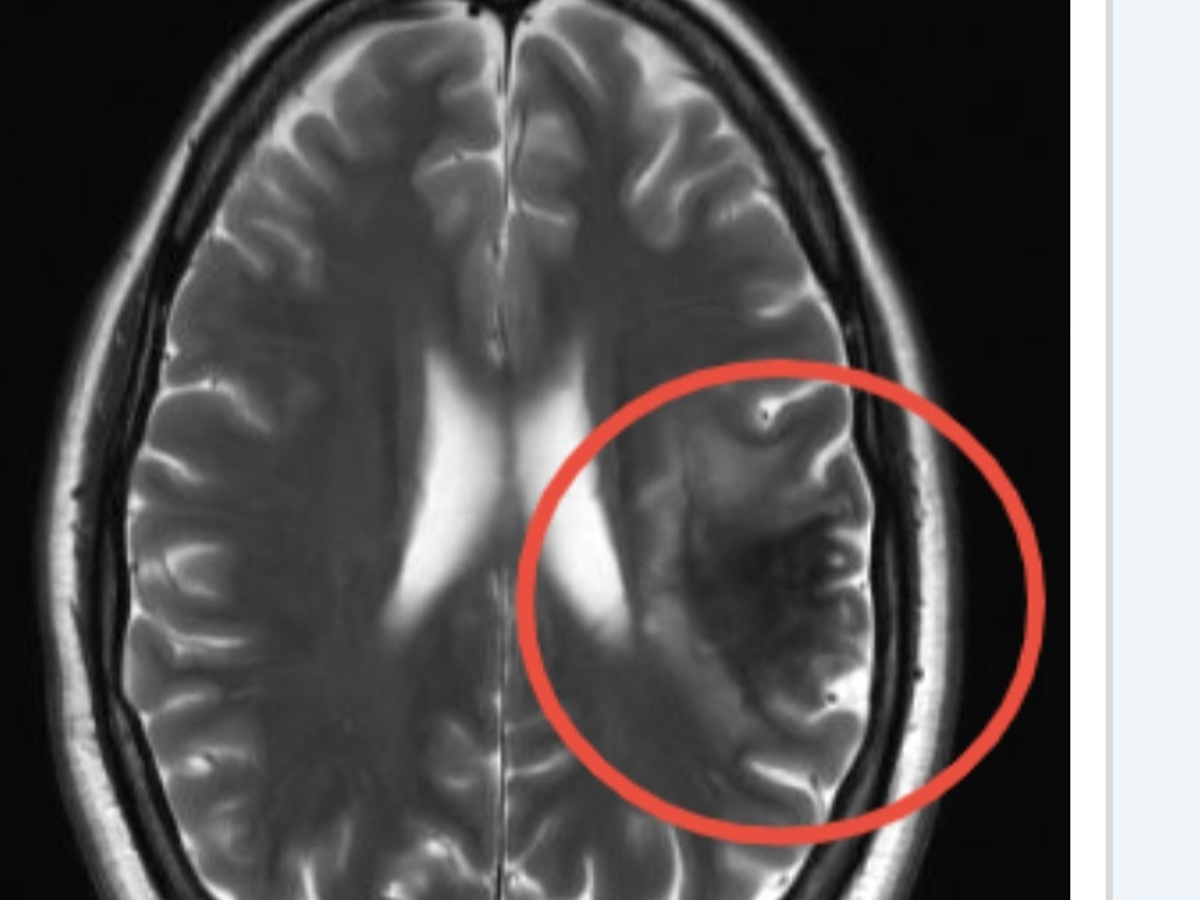

Hey guys, as most of yall know, I had a stroke in September, four months after daddy Phil passed away. I got my check up and my neurologist says I about 6 more months for my brain to heal...my right side isn't working like it should, my speech is still bad and I have a hard time still understanding tasks, im definitely getting better but it's a slow process. Me and Biscuit have been doing our best to take care of ourself, but once again we are asking for a little help until I get well again to go back to work...the universe is definitely putting me to the test, but I will not give up and throw in the towel! Thank yall and we love yall to the moon..and thank you for rooting for us with everything we've gone through!